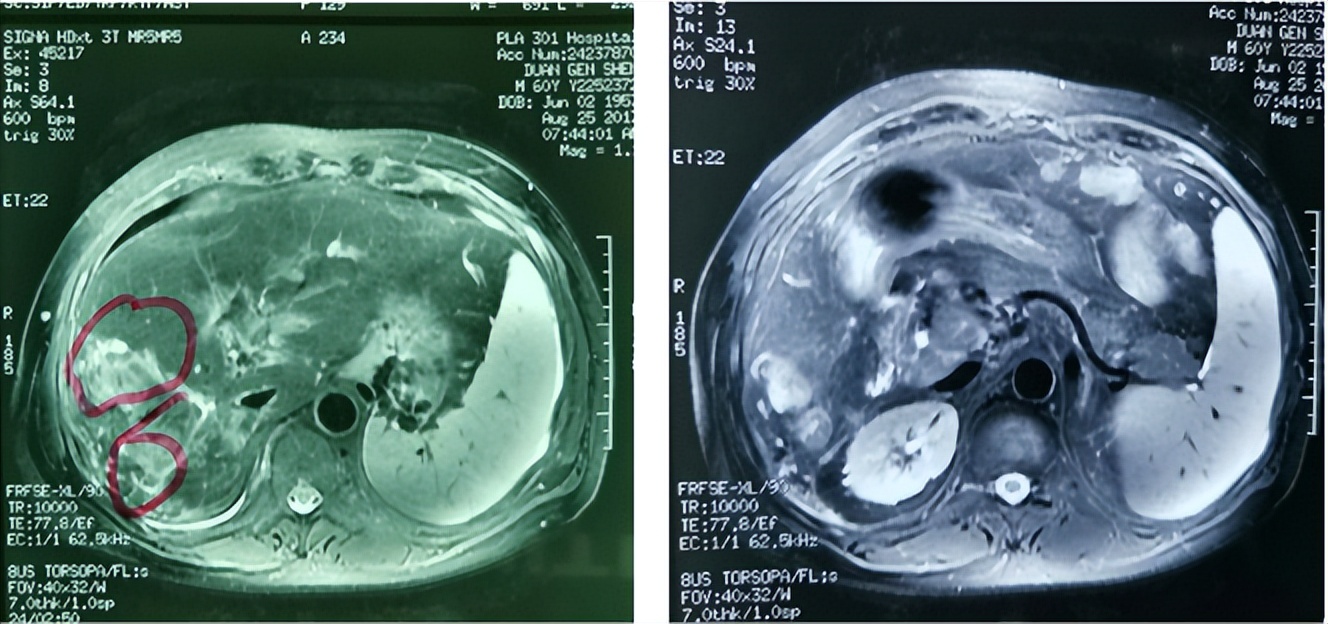

2016年8月16日,腹部MR显示,肝体积尚可,肝内见弥漫分布约3 mm以下短T2信号,肝右叶见多发约31、30、29 mm以下稍长T1、稍长T2异常信号影,DWI呈异常稍高信号,反相位图像病变信号及肝实质信号未见明显降低;动脉期病灶轻至中度不均匀异常强化,门静脉期和延迟期廓清。

肝门部门静脉、门静脉右支及主干见充盈缺损影,DWI呈高信号,动脉期轻度异常强化。 肝静脉、下腔静脉未见充盈缺损影。肝右叶及肝左内叶见多发约7 mm以下长T1、长T2信号,增强扫描未见强化。

肝内外胆管、胰管未见异常狭窄或扩张。脾脏增大,未见异常强化。胆囊、胰腺及双侧肾上腺未见异常,肝门及所见腹膜后未见明确肿大淋巴结(图1、图2)。

图1. 基线腹部MR表现

图2. 基线腹部MR表现